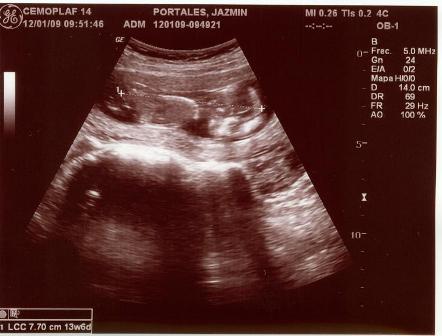

Fotos del 19 En 2009:

Informe:

Embarazo con feto de 13 semanas 4 días +/- 1 semana.

LCF: 151 lpm

Fémur: 1

Estática fetal: Variable

Movimientos: Activos normales

Placenta: Anterior lateral izquierda grado 0

Líquido Anmiótico: Cantidad normal

Impresión: Feto único, vivo con movimientos normales y actividad cardiaca normal. OCI cerrado.

Ovarios normales y fondo de saco de Douglas libre.